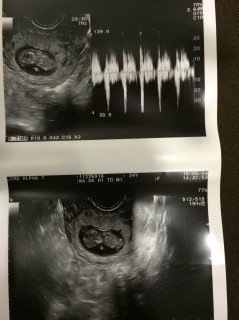

大きさわ22.2

この日に予定日が決まって

母子手帳を貰いに行った^^

心臓が動いてて、すごく感動した!

頭からおしりまでの大きさは19.8ミリ

こんなちぃさな体で手足をウニョウニョ動かしている姿を見せてくれました!

予定日も決まり、母子手帳ももらいに行けます。

赤ちゃん22mmまで育ってくれてました! 5wから水も飲めないひどいつわりがあったのですが、8wに入るころにケロっと治って。嬉しい反面もしかして…と、とても不安でしたが成長してくれてて本当に嬉しかったです!